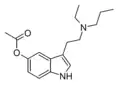

| 5-AcO-EPT [10] | artificial | 5-OCOCH3 | CH2CH3 | CH2CH2CH3 | 5-acetoxy-N-ethyl-N-propyltryptamine | |